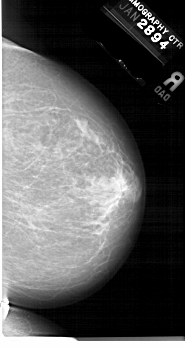

A_1679_1.LEFT_CC

LEFT_CC LINES 6631 PIXELS_PER_LINE 3346 BITS_PER_PIXEL 12 RESOLUTION 43.5 OVERLAY